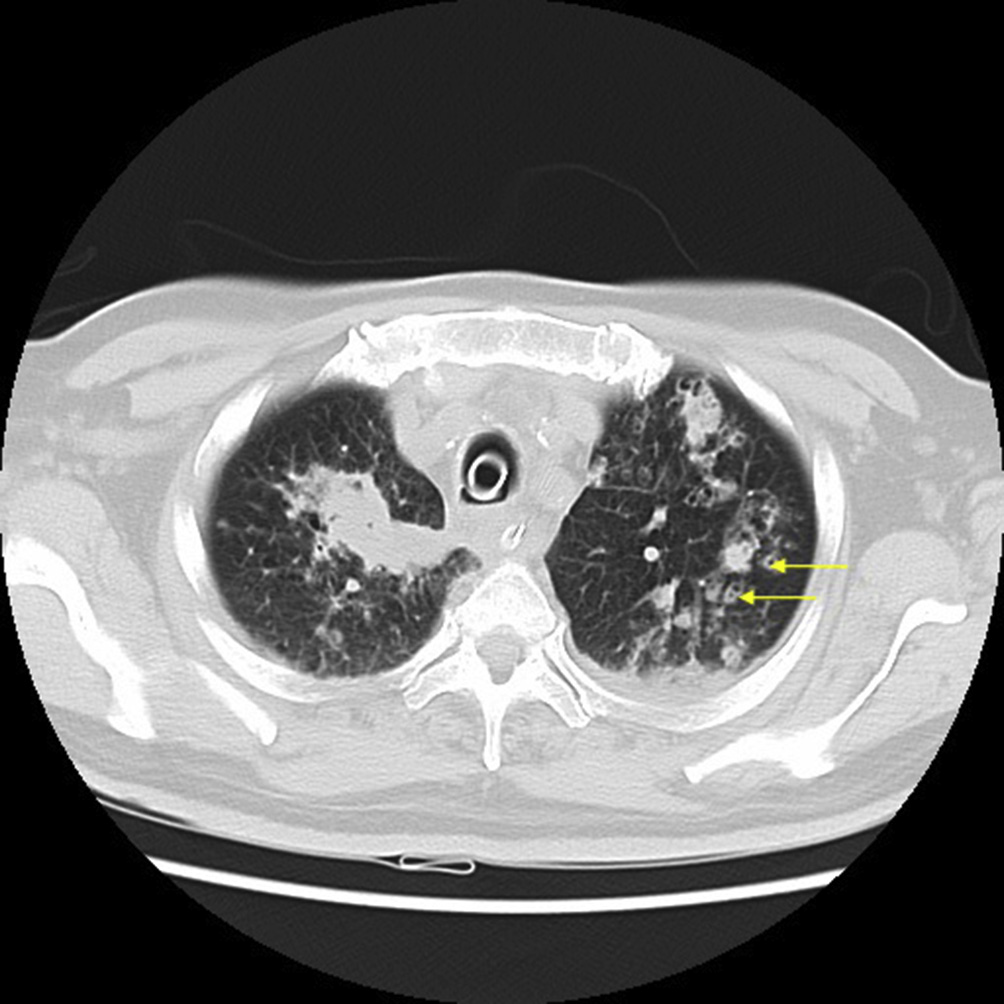

Although HRCT plays an important role in the diagnosis of pulmonary nocardiosis, variations in HRCT findings have not correlated with clinical diagnosis. Here, we describe the radiological features of pulmonary nocardiosis with respect to pulmonary nodules. Impaired cell-mediated immunity would increase the prevalence of infection [6], however, there was no study to examine the status of cumulative and/or daily dose of steroid treatment in patients with pulmonary nocardiosis. Case report: 70 year old patient with history of bronchial asthma presently on treatment with inhaled corticosteroid presented to emergency with complaints of cough with scanty expectoration and increase in breathlessness of 10 days duration. On examination he was tachypneic, tachycardic, had type 1 respiratory failure. Chest auscultation revealed harsh vesicular breath sound with bilateral expiratory wheeze and diminished breath sound in left infra axillary area. Chest x-ray and ultra sound revealed left mid and lower zone consolidation with minimal pleural effusion (Fig. 1). Laboratory evaluation revealed hemoglobin level of 10 g/dL. His WBC count was

Fig. 1. Bilateral nodular radio opacities with large coalescent region in left lower zone (arrow).